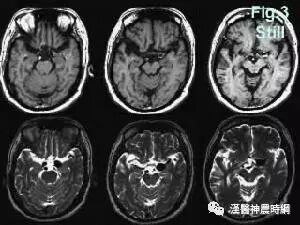

4.烟雾病 年龄多在10岁以下及20~40岁,儿童常表现为脑缺血性症状伴进行性智能低下,成人多为脑出血性症状,但意识障碍相对较轻,脑血管造影可见颅底特征性的异常血管网,以资鉴别。